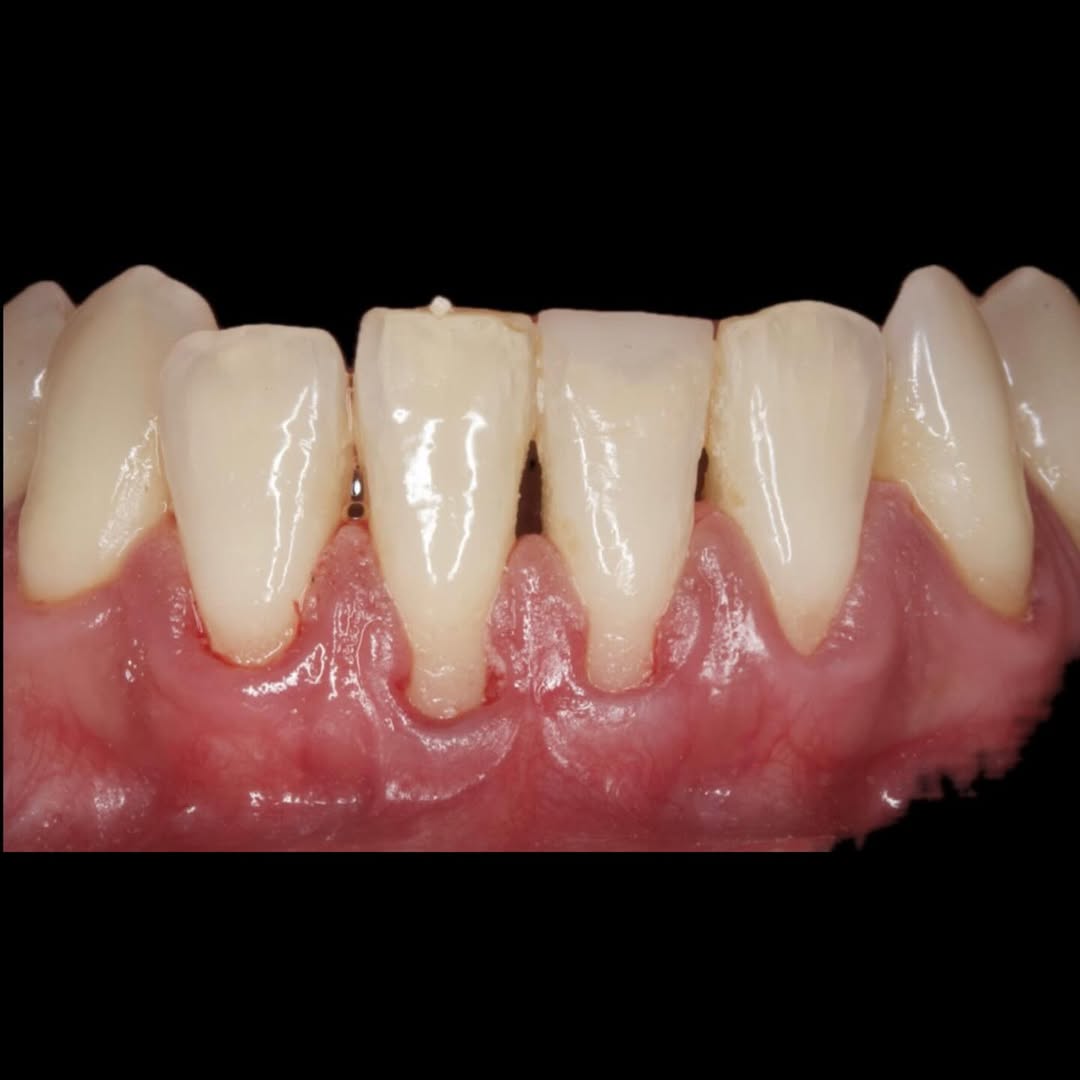

Durante una mañana, asistirás a una Cirugía Mucogingival de recubrimiento radicular de recesiones múltiples en IV y V sextante (36 a 43).

Aprende la planificación y técnica de la cirugía Mucogingival para el recubrimiento de recesiones y aumento de banda queratinizada en el sector anteroinferior